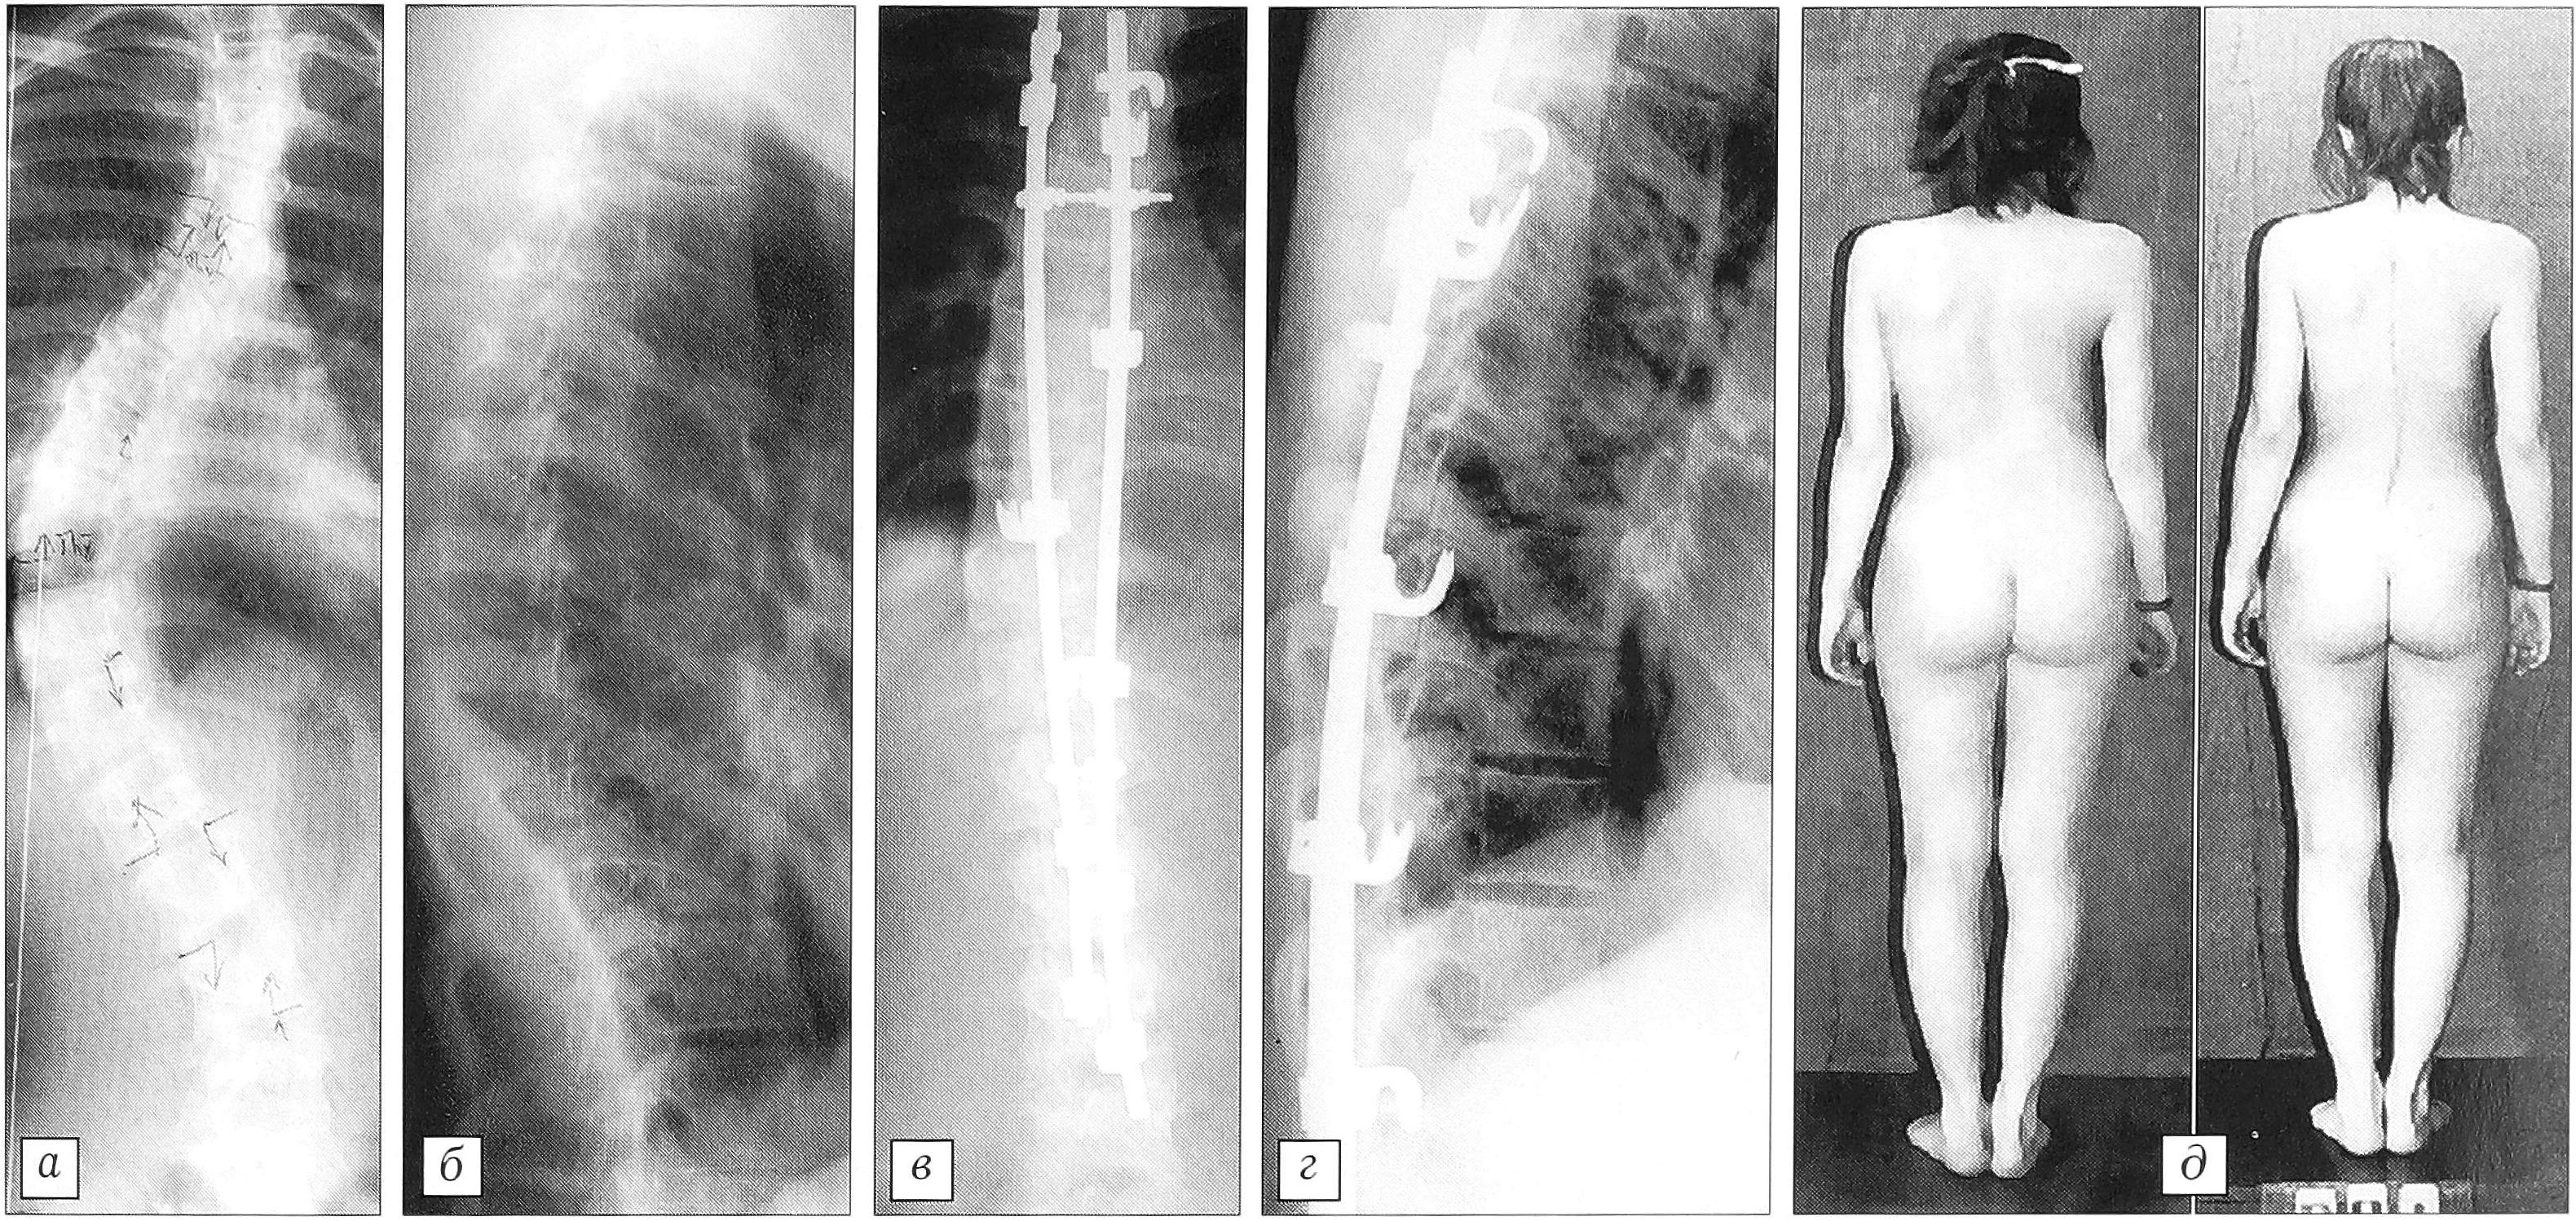

У таких больных мы считаем показанным двухэтапное вмешательство, включающее: 1) дискэктомию и межтеловой спондилодез аутокостью на протяжении основной дуги искривления; 2) коррекцию деформации сегментарным инструментарием в классической компоновке и задний спондилодез аутокостью. Вентральный этап хирургического лечения играет здесь двоякую роль: главное — формирование костного блока с целью профилактики развития феномена «коленчатого вала», второе (в данном случае менее существенное) — дополнительная мобилизация позвоночника перед корригирующим этапом. Такая операция позволяет в значительной степени исправить деформацию, а кроме того, обеспечить профилактику развития «феномена коленчатого вала» (рис. 3).

Рис. 3. Больная П-ва 12 лет (промежуточная группа). Коррекция первичной дуги в результате двухэтапного вмешательства с 66° (а) до 28° (б). Срок наблюдения 3 года (в), потери коррекции не отмечено.